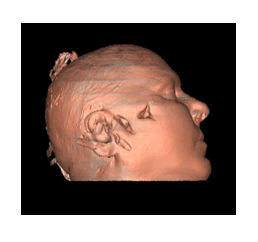

In a specific case that occurred at our facility, a TSRM was assigned the role of a defense consultant following a criminal incident. Based on the criminal charge against the defendant, a defense line was constructed by the defense attorney with the assistance of the forensic pathologist. The pathologist requested the support of a TSRM for the review of post-mortem CT images and the production of new 3D images. Following authorization from the company to undertake extracurricular justice-related assignments, 3D VR images (Figures 3 and 4) and 3D SR images (Figure 5) of the head were reconstructed from CT images produced elsewhere. Images were reconstructed for both bone tissue visualization and skin in various projections and sections to highlight the lesions of interest. Measurements of lesion dimensions and Hounsfield Units (HU) were then made on these images.

Figure 3. (Left) 3D VR reconstruction of the cranial vault. (Center) 3D VR reconstruction of the cranial vault from another perspective. (Right) 3D VR reconstruction of the cranial vault with a lateral view.

Figure 4. (Left) 3D slicer VR reconstruction of the cranial vault with a bottom view. (Center) 3D slicer VR reconstruction of the cranial vault from another perspective. (Right) 3D slicer VR reconstruction of the cranial vault with a lateral view.

Figure 5. 3D SR reconstruction of the head district with a lateral view of a model of the skin surface of the head of the body under examination.